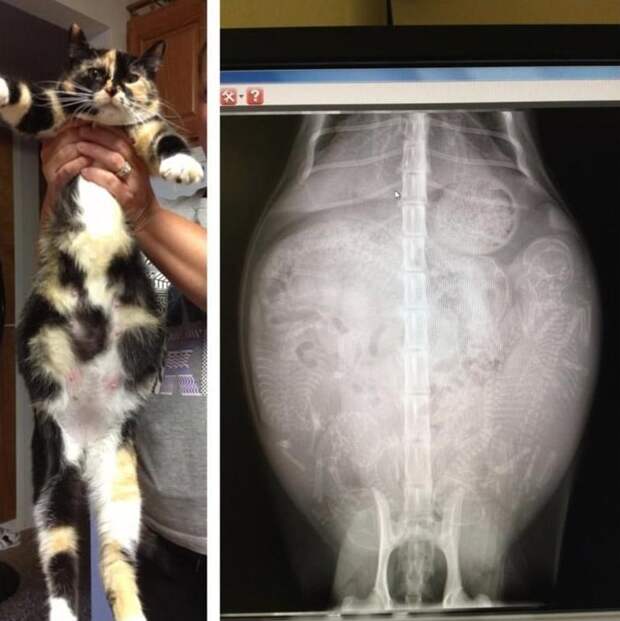

3. Беременная кошка

4. Ещё одна кошка